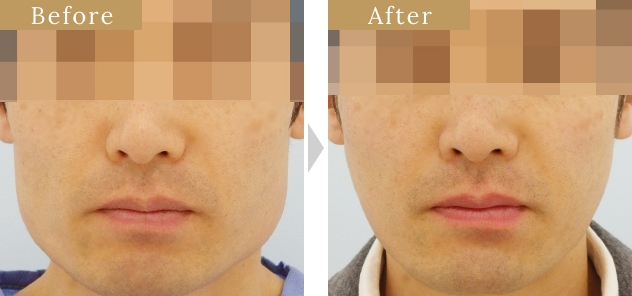

症例